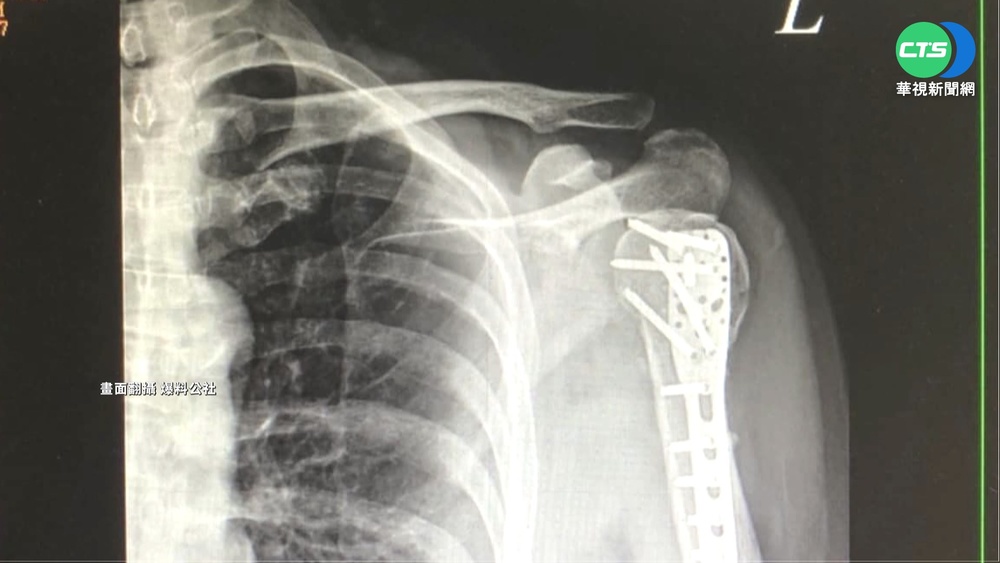

好幾張X光片,明顯看出民眾左肩骨折,用骨釘固定,會發生意外,全因為被超商補貨籃絆倒,莊小姐上網發文,說家人在超商買晚餐,轉身要結帳時,被放在地上的空籃給絆倒,跌倒後左手撞擊地板,當場聽到骨頭斷裂的喀喀聲,傷者家屬莊小姐說:「區顧問的莊小姐,然後跟另外還有一個同事,好像也是區顧問一個先生,他們倆個其實就是當天,就是在現場其實都有陪同我們,在那邊等待醫師的問診,然後他們也跟我們說,公司是有保險的,然後說他們會負責任,就是理賠這件事情。」